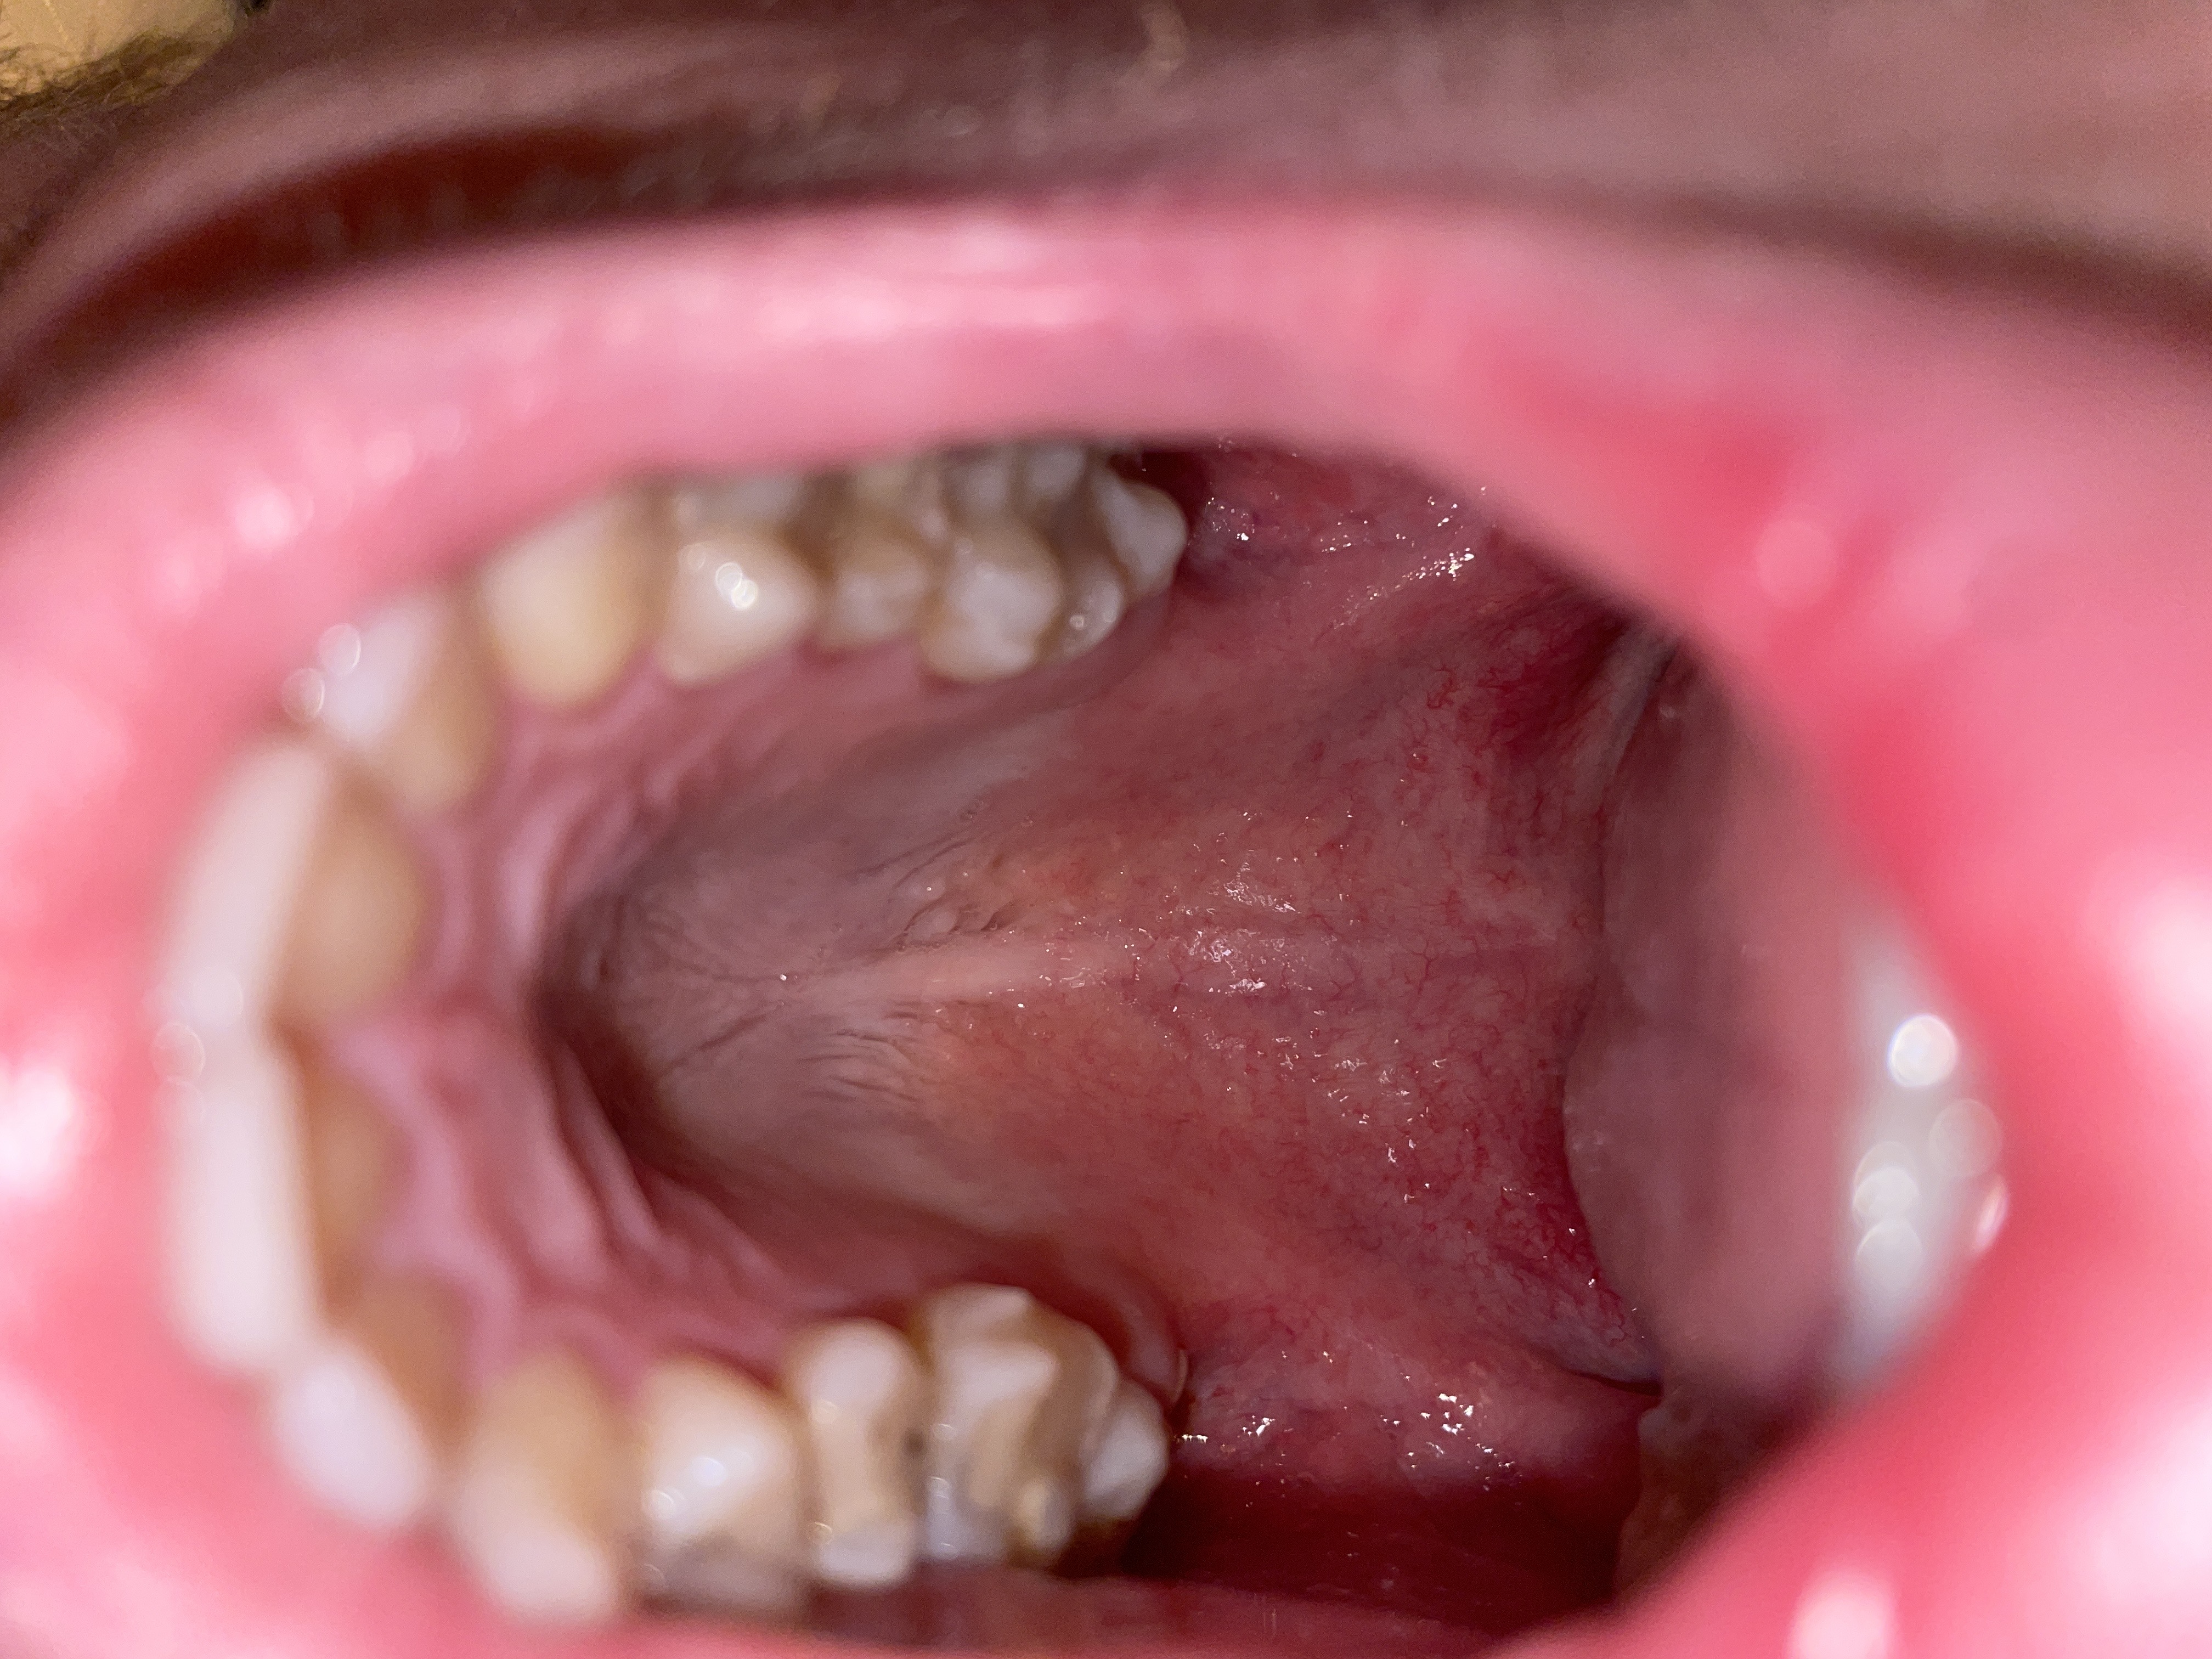

Ik heb heel veel keelpijn/pijn bij m’n gehemelte. Pijn bij slikken. Is hier ook iets zichtbaar en hoort dit erbij?

Denk niet dat keelpijn hier bij hoort tenzij alleen aan de kant v extractie. Maar er is aan 4 zijden getrokken dus mogerlijk. Als het aanhoudt laten beoordelen na min een week??.